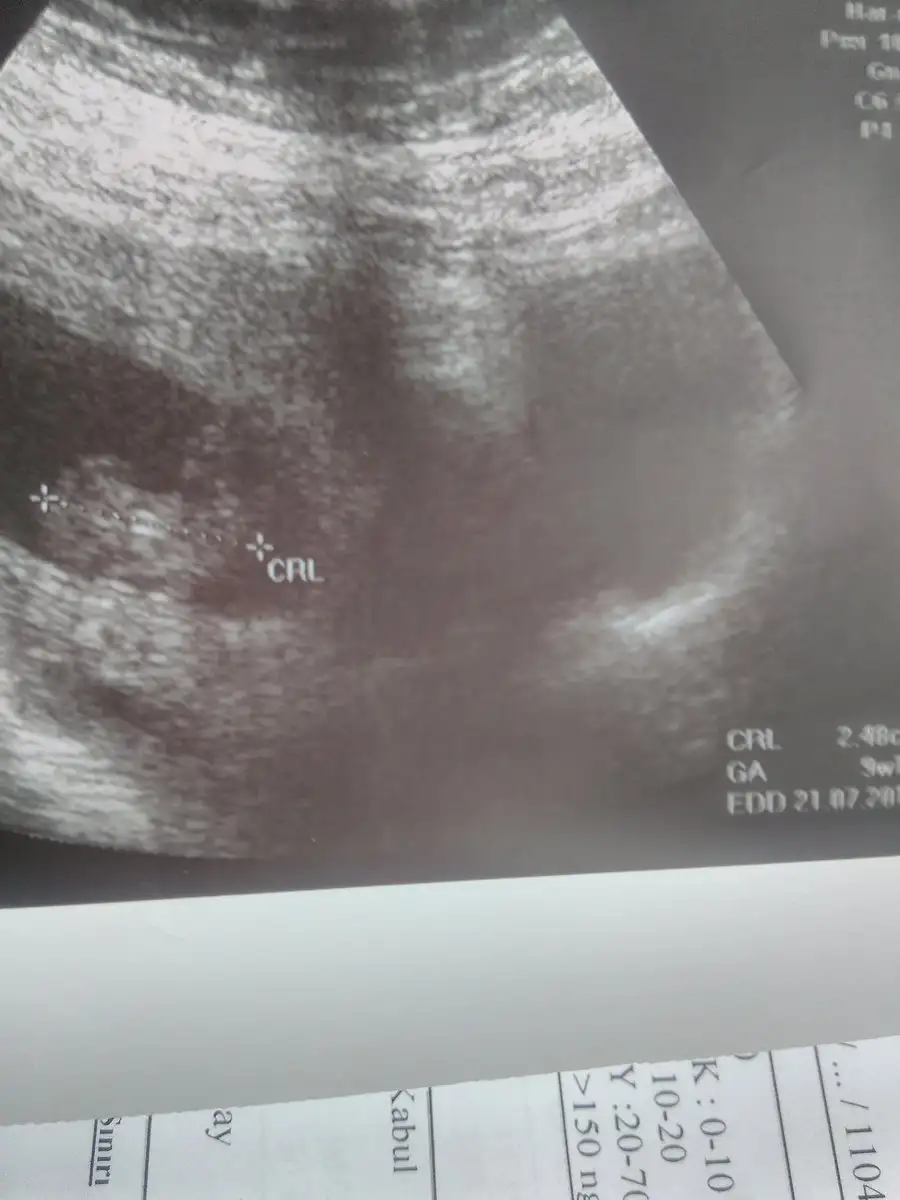

Canım emin olamadım. 11 yada 12 haftalık ultrason resmi alirsan beni etiketlersen sevinirim. Bende merak ettim.

Tamm cnm 14 15 haftalkkken gtmeyı dsunuyorm bklmCanım emin olamadım. 11 yada 12 haftalık ultrason resmi alirsan beni etiketlersen sevinirim. Bende merak ettim.